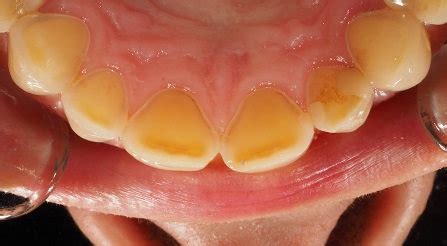

Respecto a la evaluación diagnóstica, apenas a la observación se visualicen clínicamente como erosiones o se evalúe cierto riesgo de una lesión en el tercio gingival, éste debe ser cuantificado con la mayor precisión posible. En todos los casos se debe correlacionar la observación con el relato clínico del paciente relacionado con la sintomatología (tabla 2).

El diagnóstico preciso requiere una historia clínica detallada, explorando factores de riesgo dietéticos, médicos y comportamentales. El examen clínico debe evaluar la textura superficial, el contorno y la presencia de exposición dentinaria. La documentación fotográfica y los modelos de estudio seriados facilitan la detección de cambios progresivos.

En este caso se utilizó la nueva tecnología de resinas con modulador de contracción, que permite bajar el nivel de stress de polimerización mejorando la adaptación de la misma a la superficie dentaria, disminuyendo la sensibilidad postoperatoria.